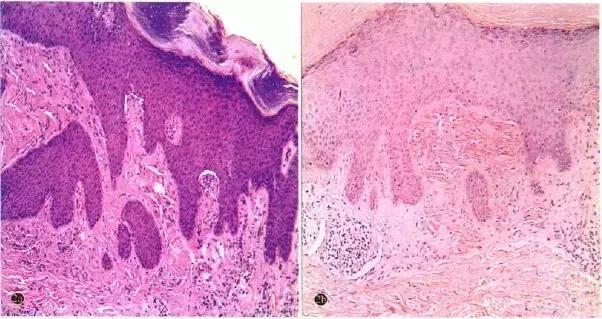

胸部X线片、心电图正常;肿瘤抗原、癌胚抗原正常。上臂及大腿皮损组织病理检查:表皮鳞状上皮增生及角化过度,真皮乳头内粉红色无定形透明样物质沉积,真皮乳头和浅层吋见稀疏炎性细胞浸润;无定形透明样物质刚果红染色呈砖红色(图2)。

图2 患者上臂皮损组织病理 2a)角化过度,棘层肥厚,颗粒层增厚,真皮乳头内可见粉红色无定形透明样物质沉积(HE染色*100);2b)刚果红染色阳性(刚果红染色*100)